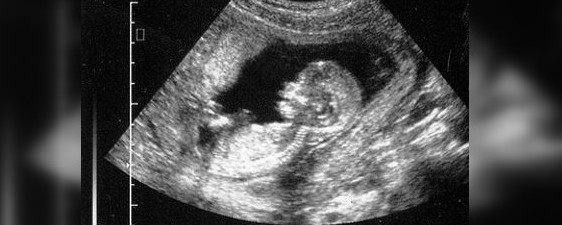

Житель Кара-Бууры А.Калматов и его супруга написали заявление на гинеколога, считая её ответственной за выкидыш